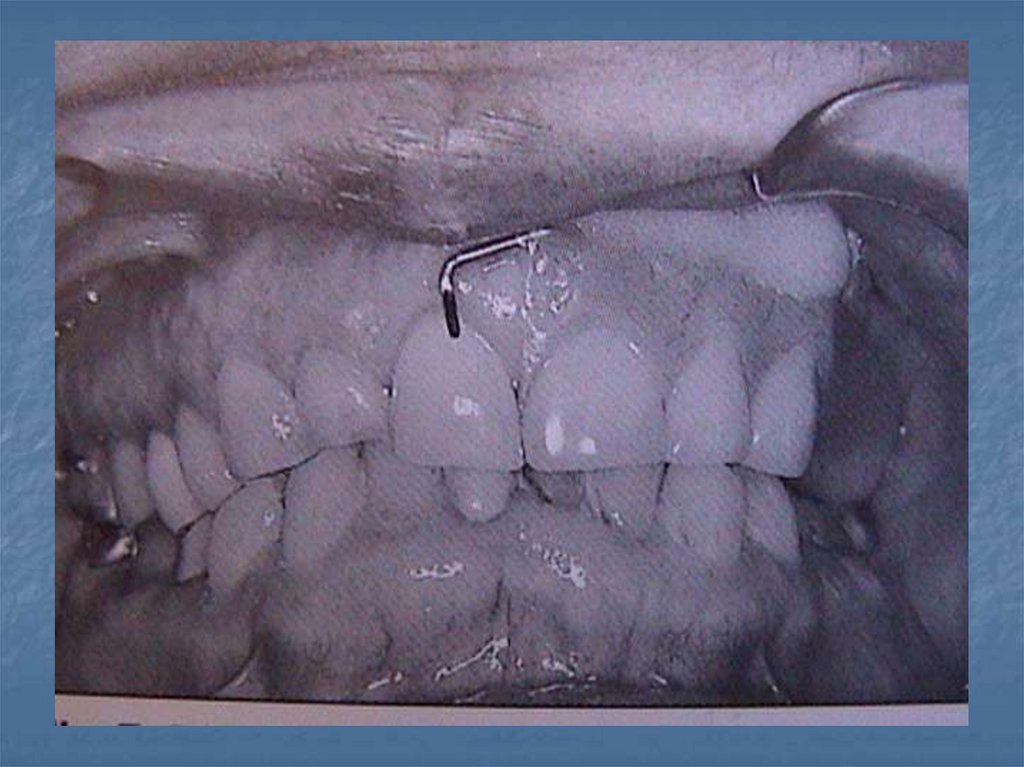

54. Daimi obtüratörler

Ameliyattan 8-12 hafta sonra uygulanan

protezlerdir.protez için gerekli bütün

ayrıntıları taşırlar.

Bu protezlerden sonra hasta ışın tedavisine

tabi tutulursa protezle dokuların uyumu

bozulacağından daimilik özelliği kaybolur.